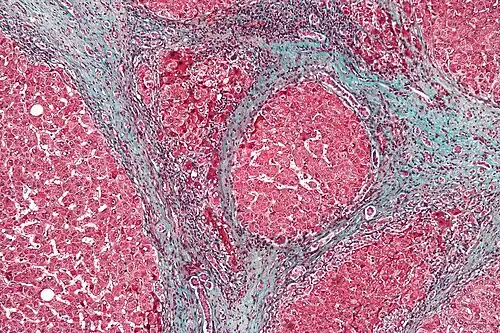

Les prélèvements subissent plusieurs colorations : éosine-safran, trichrome de Masson, de Perls et le PAS. Une mesure du poids en fer et la recherche d'antigènes viraux peuvent être faites.

Anatomopathologie

L'histologie de la cirrhose montre une fibrose en pont délimitant des nodules de régénération, fait de travées bicellulaires d'hépatocytes parfois dysplasiques.

Le foie peut être atrophié (diminué de volume) ou inversement hypertrophié (augmenté de volume) en fonction de la prédominance de lésions de destructions ou de régénérations.

D'autres lésions sont visibles, elles sont caractéristiques des mécanismes à l'origine de la cirrhose. Lors d'une cirrhose alcoolique, il existe une stéatose macrovésiculaire hépatique, des signes d'inflammation avec une infiltration de lymphocytes et de macrophages, la présence de corps de Mallory, une nécrose des cellules hépatiques, des mitochondries géantes, une hépatosidérose. La maladie de Wilson se caractérise par un dépôts de cuivre dans les hépatocytes, l'hémochromatose par des dépôts d'hémosidérine, la cirrhose biliaire primitive par une modification des travées des canaux biliaires.